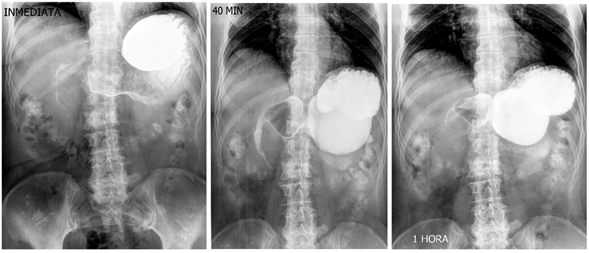

Esophagogastroduodenal series (30.09.2021): Gastroesophageal reflux GII, hiatal hernia type 1, gastric inflammatory process (Figure 1).

Figure 1 Esophago-gastro-duodenal series: Gastroesophageal reflux GII, duodenal stenosis, gastric inflammatory process, expiration of the ileocecal valve three hours after the start of the study.